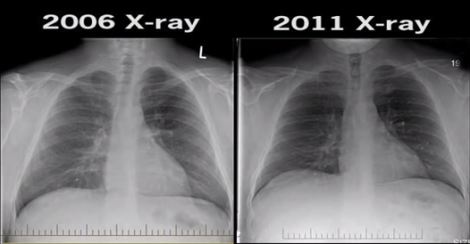

Researchers tested the effects of nicotine on lung tissue growing in a lab dish. Those lung cells were exposed to nicotine alone, in cigarette smoke and in e-cigarette vapors. Follow-up tests exposed lab animals to these same substances. Nicotine caused inflammation in lung tissue. It also reduced that tissue’s ability to serve as a barrier to foreign substances, the researchers found. Irina Petrache is a doctor and lung specialist at Indiana University in Indianapolis. She headed the research team. Her group showed for the first time that nicotine, whatever its source, can harm lung tissue. So in this respect, her team now concludes, vaping would be no better for the lungs than cigarette smoking.